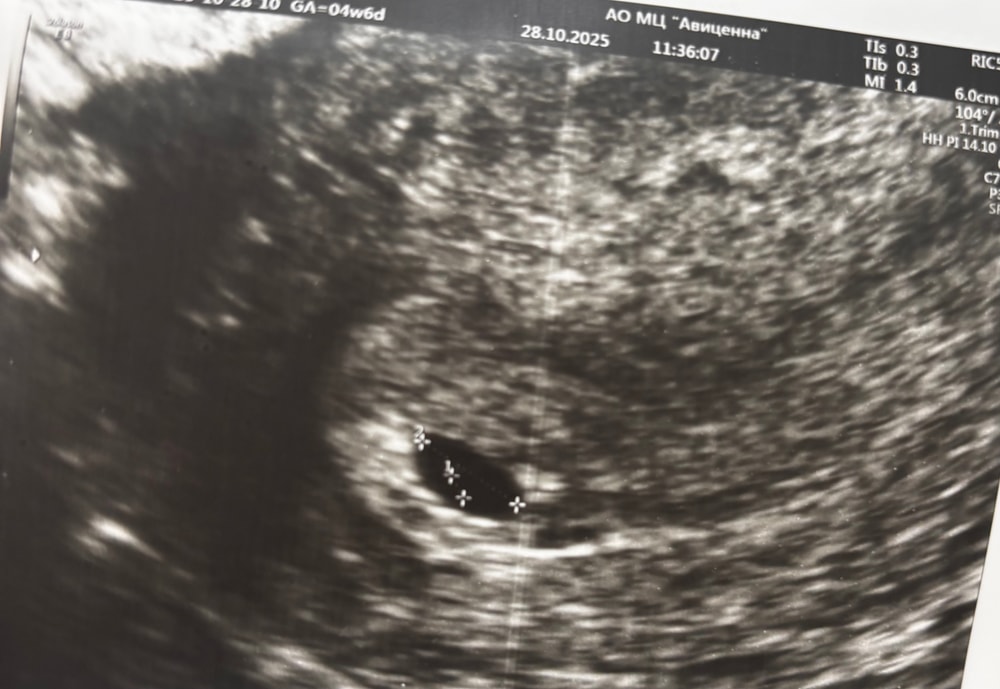

Юлия, узист напугал, говорит деформировано, овальное

Форма как форма, оно такое и есть, чуть продолговатое:) плюс еще зависит от того, как узист фото сделал)